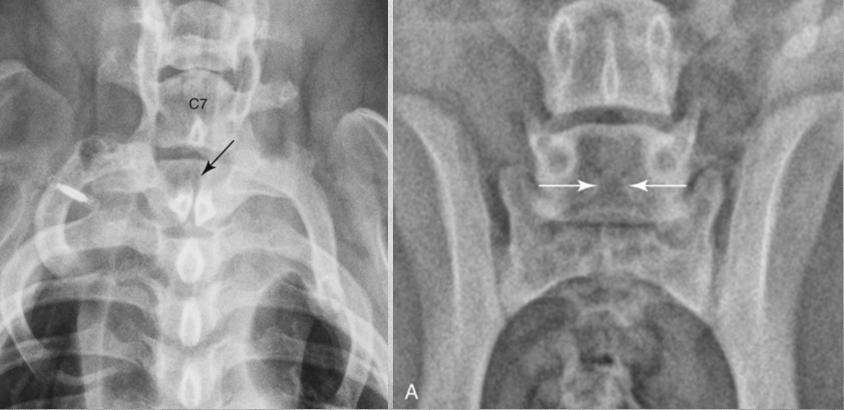

19

Q

identify anomaly

A

transitional vertebrae

Abnormal vertebra that Shares characteristics with those from an adjacent vertebral segment (can be rudimentary).

When in Lumbosacral area - problematic.

Can be a lumbar vertebra having a rib when it shouldn’t. (right image)

breed predilection, GSD